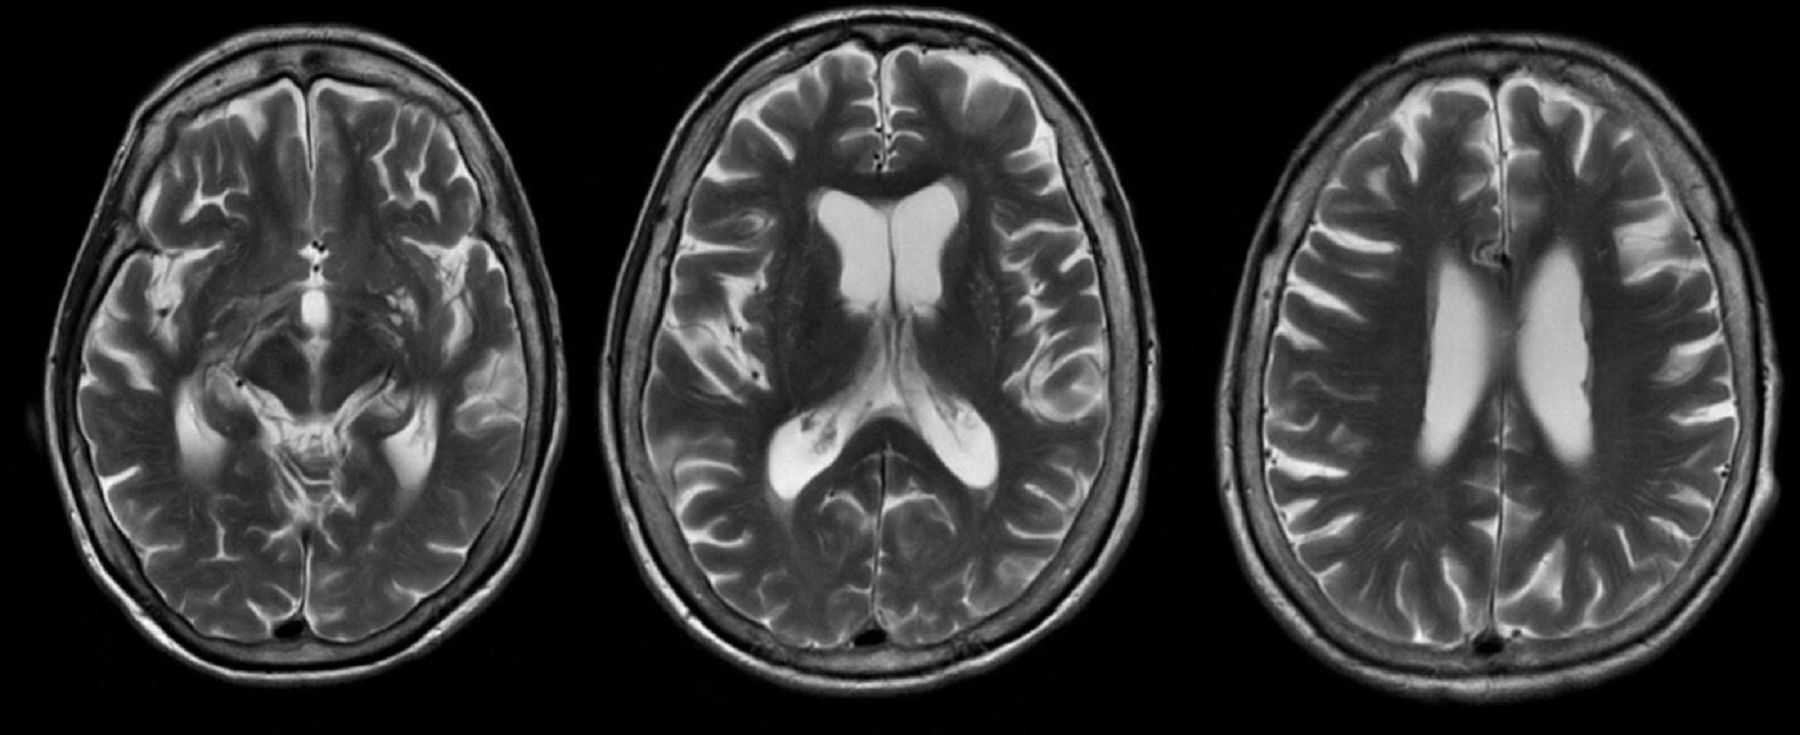

Демиелинизирующие заболевания мозга: МРТ изображения